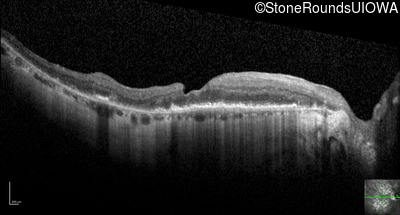

Optical Coherence Tomography - Right - 20/25 -1

Exemplar / OCT Stack